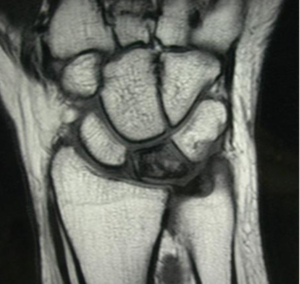

• MRI: An MRI may be used to further assess the condition of the lunate bone and to check for any other underlying conditions that may be contributing to the symptoms.